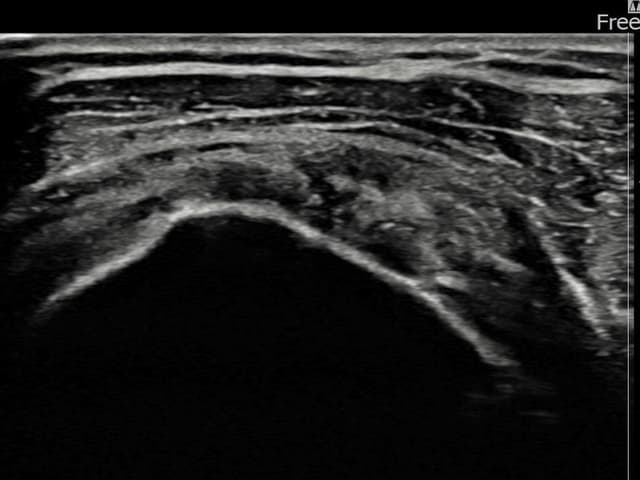

[촬영시기:24.01.08~24.03.14]

[어깨인대 축소봉합술] 좌측 어깨 통증으로 팔을 올리기 불편하여 내원하셨습니다.